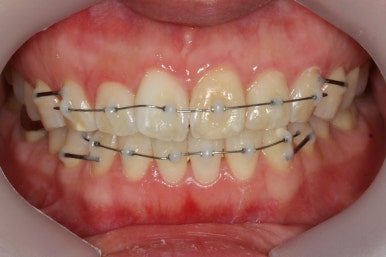

장치를 처음 부착하고 두 번째 조절을 했을 때의 사진입니다.

부분교정의 경우 치료기간을 앞당기기 위해 3주의 내원간격으로 하는 경우가 많은데, 이번의 경우는 결혼식까지 남은 시간이 너무 촉박하여 완벽히 치료를 끝내지 못할 가능성이 컸습니다.

세 번째 조절입니다.

가지런한 정도는 매우 좋아졌고, 군데군데 틈새가 있어서 조여주고 있는 상황입니다.

이정도만 되어도 결혼식을 진행하시기에 어느 정도 만족도 있는 수준까지 왔다고 생각되어졌습니다.